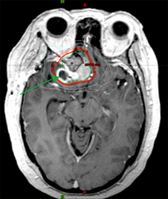

Benign brain tumor (memingioma, green arrows) compressing and affecting optic nerve (visual nerve, red arrow).

Highly focused stereostatic radiotherapy plan, treating the benign brain tumor (meningioma, green arrows) to high dose while sparing the normal brain, eyes and optic nerves.